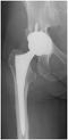

Na vertebroplastia, o cirurgião utiliza uma agulha oca para injetar uma substância semelhante a um cimento, em geral polimetil-metacrilato (metacrilato de metila) ou PMMA, em todas as rachaduras ou fraturas encontradas na coluna vertebral. Embora a osteoporose enfraqueça os ossos do corpo todo, a vertebroplastia é utilizada exclusivamente para o tratamento de problemas na coluna. O cirurgião usará também um fluoroscópio, que é composto por um aparelho de raios X e uma tela fluorescente, para monitorar a localização da agulha no interior do corpo e garantir que o selante seja injetado no local adequado.